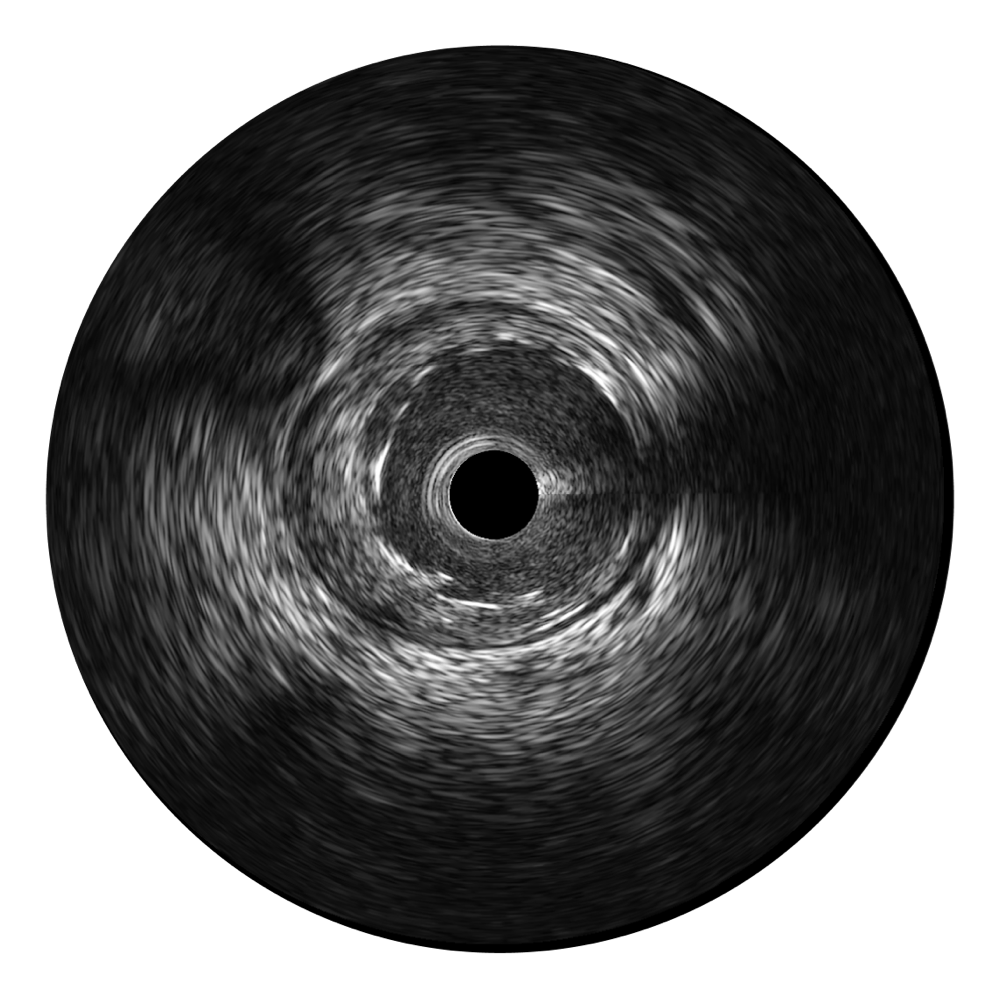

传统IVUS图像

对比传统IVUS导管成像,玖鼎集团宽频IVUS图像的近场支架梁显影更细腻,远场中膜外血管仍清晰可辨,兼顾远中近,兼顾分辨力与穿透深度